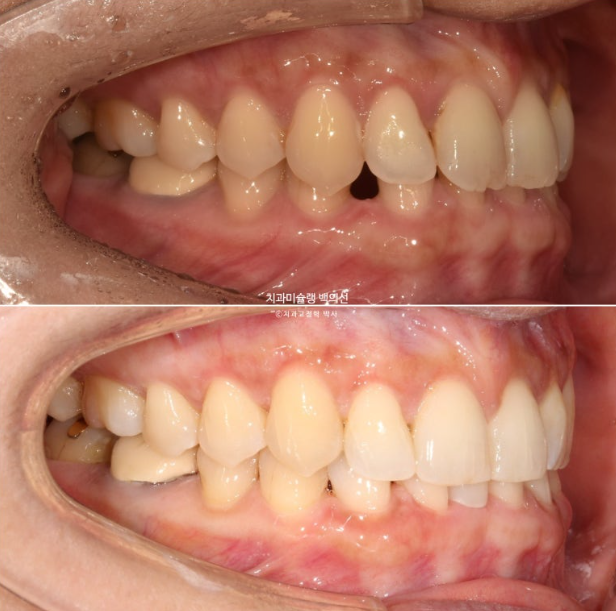

25.02

과개교합은 소량 개선되었고 아래앞니 공간은 가운데로 잘 모아졌습니다.

원래 벌어져 있던 공간은 대부분 없어졌으나 미세공간이 아직 남아있습니다.

파란화살표 쓰러져있던 큰어금니는 꽤 많이 섰습니다.

남은 공간을 정리하고 과개교합을 좀 더 개선하고자 재제작에 들어갑니다.